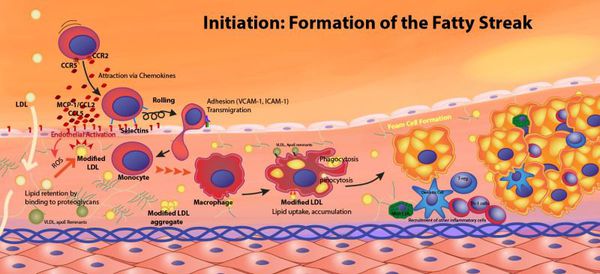

Холестерин и атеросклероз

«Генетическими поломками» вызвана так называемая семейная гиперхолестеринемия, при которой перемещающиеся в крови комплексы липидов, содержащие холестерин, плохо захватываются тканями (прежде всего, печенью). В результате концентрация в крови этих частиц и, соответственно, холестерина, возрастает, и избыточный холестерин, а также его эфиры оказываются в конечном счете в стенке артерий. Конечно, процесс этот гораздо сложнее и в действительности является многоэтапным, но конечный результат его — образование атеросклеротических бляшек в стенках сосудов.

Повышение концентрации содержащих холестерин частиц в крови может гораздо чаще происходит не в силу генетических поломок, а вследствие нездорового образа жизни.

Сам по себе холестерин — жизненно необходимое вещество, и каждая наша клетка способна его синтезировать по мере надобности. А вот когда способности организма использовать и утилизировать свой холестерин снижаются, вот тогда его концентрация в крови возрастает, со всеми дальнейшими последствиями. Снижают способность утилизировать свой собственный холестерин такие факторы, которые изменяют химический состав липидных частиц, в состав которых входит и холестерин. Это, например, курение, сахарный диабет, хроническое воспаление. Эти же факторы повреждают стенки сосудов, облегчая тем самым проникновение в них содержащих холестерин липидных частиц крови.

Патогенез атеросклероза

Рост атеросклеротических бляшек — процесс, растянутый на долгие годы и десятилетия. Если бляшка в стенке сосуда достигает значительных размеров (около 70% просвета сосуда или более того), она может создавать существенные препятствия для кровотока и для кровоснабжения соответствующего органа — например, сердца или мозга. Бляшки, небольшие по размерам, тоже небезопасны — при разрыве таких бляшек (это возможно в случаях, когда истончается по разным причинам их «покрышка») в месте разрыва возникает образование тромба, который может полностью перекрыть просвет сосуда. [5] В этом случае из-за резкого ограничения кровотока возникает гибель значительного количества клеток органа, кровоснабжаемого данным сосудом — инфаркт (например, инфаркт миокарда или инфаркт мозга — инсульт, возникающий при атеросклерозе сосудов головного мозга).